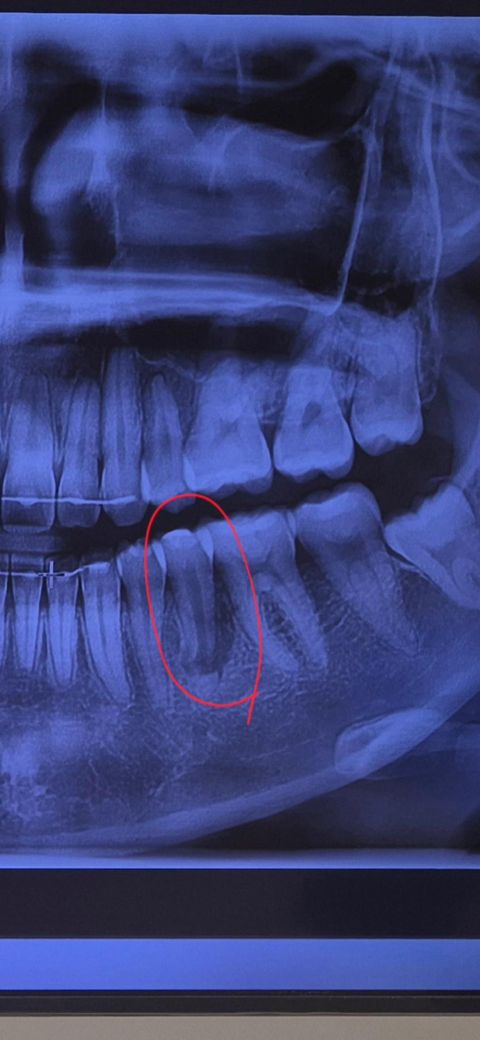

교정 끝난지 얼마 안되었는데 유지장치 제작을 위해 사랑니를 발치하라고 해서 사랑니치과에 내원했습니다. 거기서 엑스레이를 찍었는데 동그라미 친 치아의 신경?뿌리?가 끊긴것 같다고 신경치료도 못하고 이를 뽑아야한다는 말을 들었습니다.. 유독 까맣게 보이긴 하는데 정말 끊어진건가요?

엑스레이 상으로는 동그라미친 치아의 주변 잇몸뼈가 많이 녹아 잇는 상태 같습니다 저정도면 발치를 해야될 가능성이 높아 보입니다.

신경 뿌리 부분의 끝 부분이 흡수된 것으로 보여집니다. 또한 해당 부분의 염증으로 인하여 뼈 소실도 상당한 것으로 보입니다. 1차적으로 dental-ct 등을 촬영하여 치아 자체에 큰 문제가 없다면 신경치료를 시도해볼 수 있으나 발치 가능성을 열어두고 치료를 이어가야할 것으로 보여집니다.

사진만 봤을 때에는 치아 주변의 뼈가 많이 녹아보입니다. 증상이 없으면 바로 빼기보단 신경치료 후 지켜볼 것 같습니다.

치아뿌리끝 즉 치근단이 모아지지 못하고 벌어져 있는 상태이며 치아뿌리 주변으로 염증이 커게 잡혀 있습니다. 일단 신경치료는 한번 해 보는 것이 좋지만 신경치료 안될 가능성도 있습니다. 신경치료 결과 안좋으면 뽑고 임플란트 생각해야 합니다.